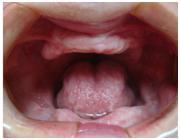

- Extreme gum infection which has resulted in severe mobility of all the teeth.

- Most of the teeth are decayed and beyond repair.